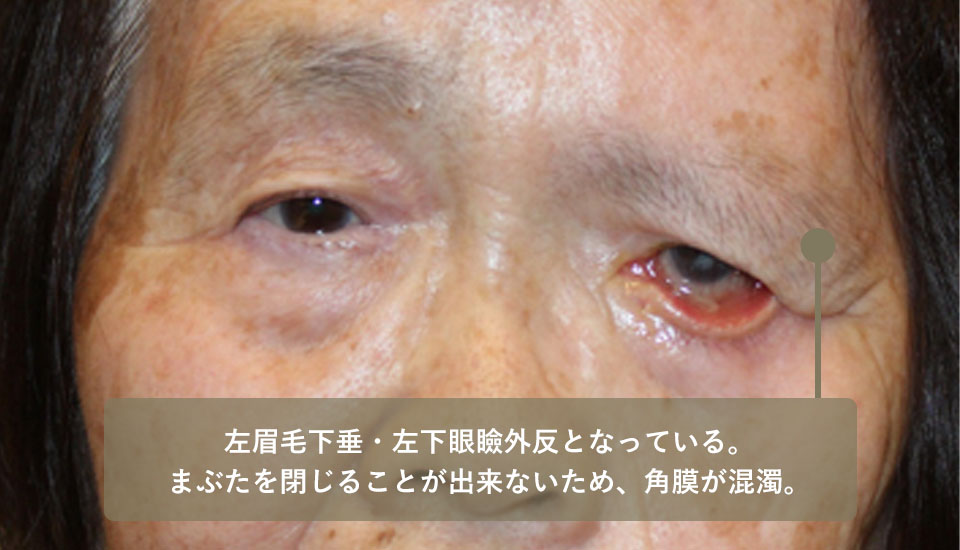

左顔面神経麻痺があるため左眉毛下垂による左視野障害をきたしていたため、前医G眼科にて左睫毛上皮膚切除を受けたがこれ以上の改善は困難とのことで紹介されました。

左眉毛下垂があり眉毛挙上術が望ましい状態でしたが、左上眼瞼皮膚がすでに切除されていたため眉毛挙上を単独で行うことが出来ず、右上眼瞼からの皮膚移植を同時に行っています。

順次、左下眼瞼外反の手術、右のほうれい線へのヒアルロン酸注射も行うことで顔貌の改善を得ることが出来ました。

| 術前 | 左眉毛下垂・左下眼瞼外反となっている。 まぶたを閉じることが出来ないため、角膜が混濁してしまっている。 |

|---|---|

| 術後 | 左眉毛下垂・左下眼瞼外反があり、まぶたの裏が露出してしまっている |

こちらは初めて当院へお越しいただいた時の治療前の写真です。

前医で左上まぶたの皮膚切除を受けたため、上まぶたの量が左右で大きく異なる。

術後、かなり見た目が改善されました。

左眉毛を上げる手術、右上まぶたから左上まぶたへの皮膚移植、左下まぶたの外反手術を行いました。

また、ほうれい線へのヒアルロン酸注射もしています。

| 主訴 | 左眉毛下垂・左下眼瞼外反となっている。 まぶたを閉じることが出来ないため、角膜が混濁してしまっている。 |